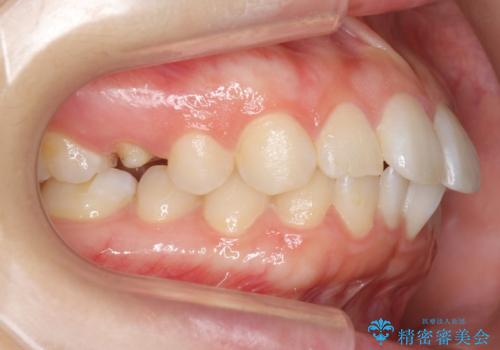

前歯のがたつき インビザラインで

- 前歯のがたつきを治したいとのことでした。歯を抜かずにできる範囲で引っ込めたいとのことでした。

歯列の側方拡大(横に広げる)と、エナメル質の削合で並べました。

右上4番目の被せ物の治療については以下で紹介しています。

歯を抜いているわけではないので、口元はそこまで変化はありませんが、前に出すことなくデコボコは取れたと思います。